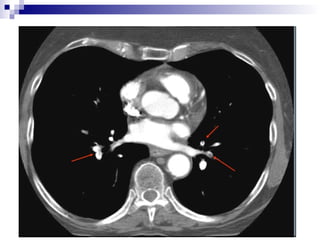

Spiral CT

• Direct visualization of emboli.

• Both parenchymal and mediastinal

structures can be evaluated.

• Offers differential diagnosis in 2/3 of cases